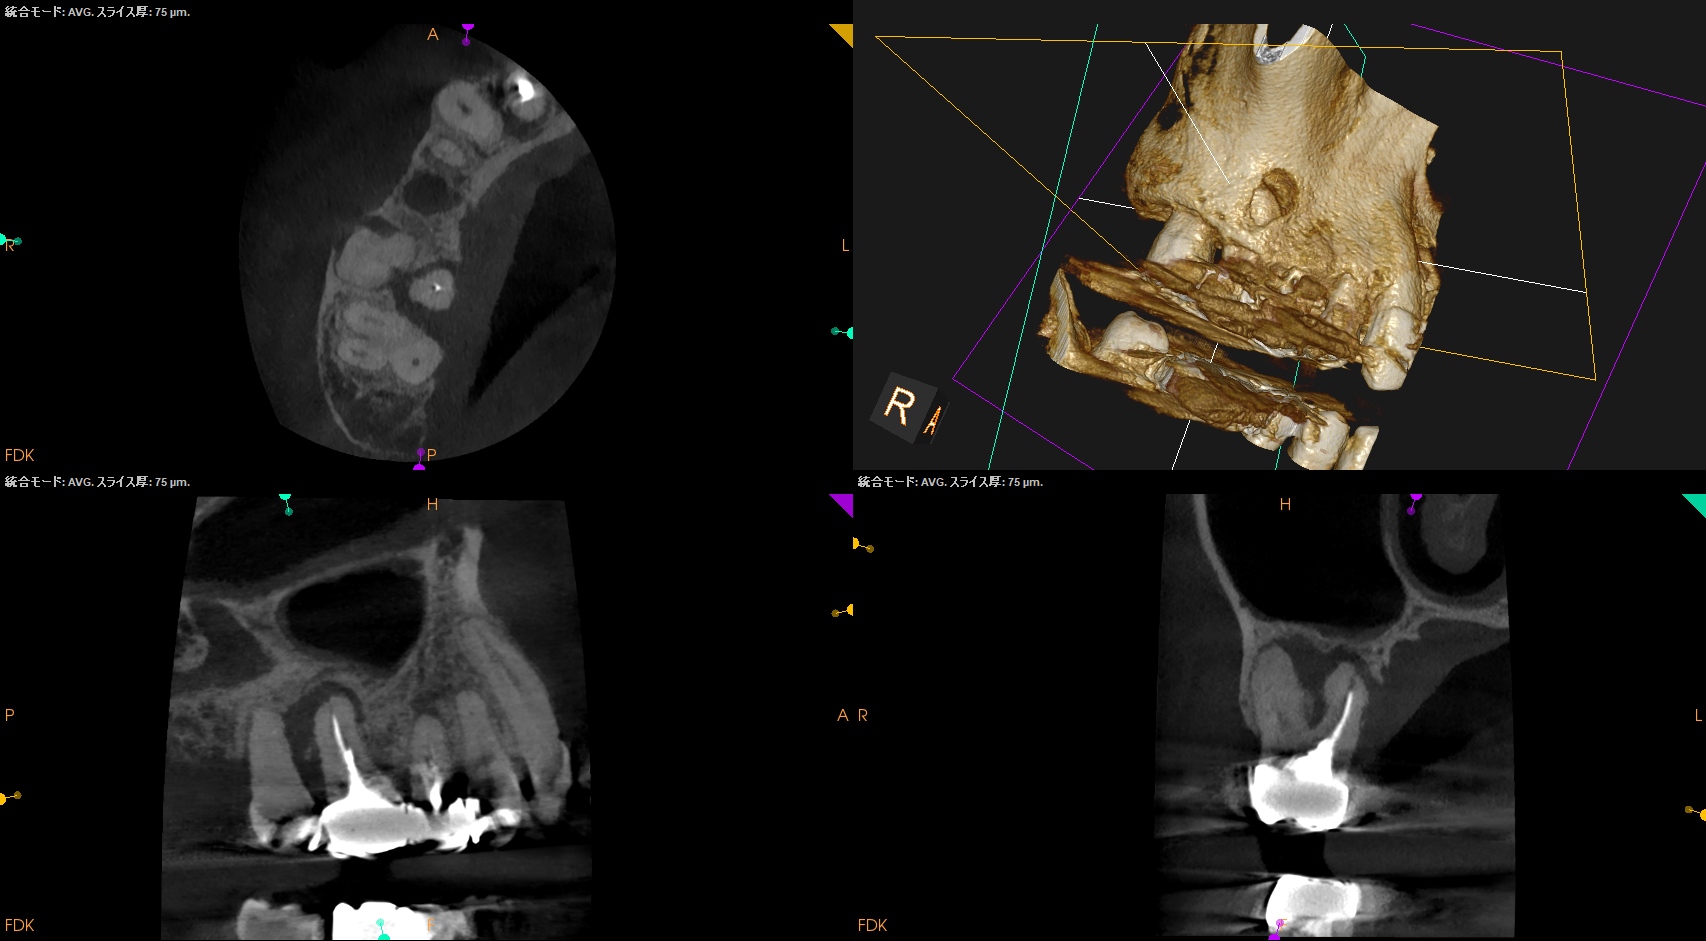

CBCT(2025.9.22)

#4

#3 MB

DB

P

これで抜歯とは…意味がわからない。

このCBCTの絵でこの結果が想像できるだろうか?

このことから何が言えるか?と言えば、

CBCT画像からのみ根尖部の解剖学的形態・状態を推し量るのは無理である

という臨床的事実だ。

再根管治療は実際にFileを根管の中に入れないとそれに意味があるかどうか?はわからないのである。